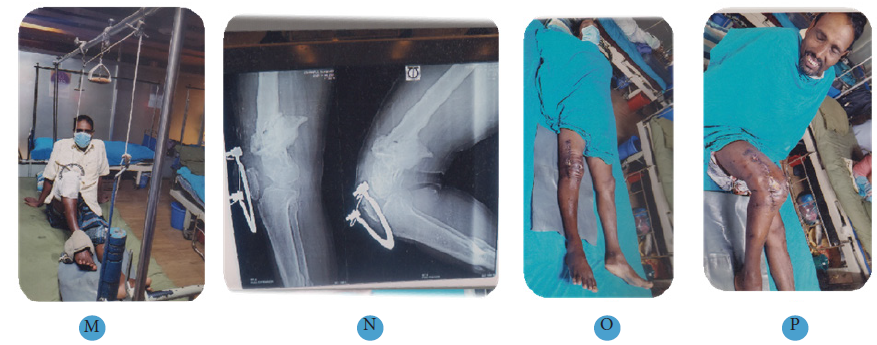

(M) Patella traction after 14 days.

(N) Radiographic view of right knee> 90o.

(O) Final follow up extension view.

(P) Final follow up flexion view.